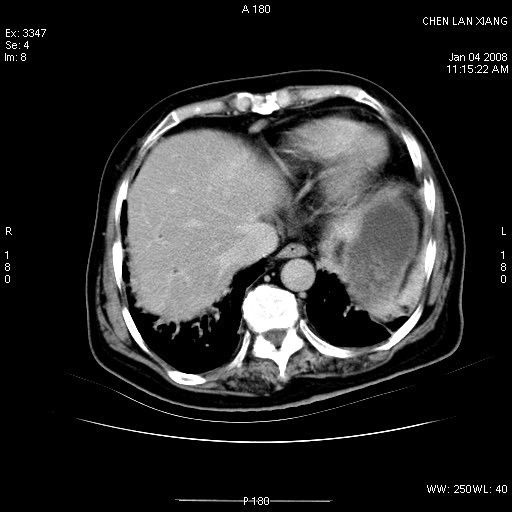

标题: CT11180:女,76岁,腹痛3-4天 [打印本页]

女,76岁,腹痛3-4天,b超示:肝内实性肿物,胆囊强回声,胆总管扩张.

考虑:1、胆总管下端结石伴梗阻性肝内外胆管扩张(肝左叶外侧段肝内胆管多发结石、胆管炎);

2、肿囊癌累及肝,不除外 黄色肉芽肿性胆囊炎。

1 胆总管末端结石伴肝内胆管结石,肝内外胆管扩张。2 胆囊扩大,胆囊壁不规则增厚,内见软组织密度影。考虑:慢性胆囊炎,不除外胆囊癌!

胆总管末端结石伴肝内胆管结石,肝内外胆管扩张。低位胆道梗阻2 胆囊扩大,胆囊壁不规则增厚,内见软组织密度影。考虑:慢性胆囊炎,不除外胆囊癌!

胆囊密度增高,增强后周边肝组织及胆囊窝下部周边软组织延时性不规则强化.然胆囊壁未见明显不规则增厚及肿块.左侧肝内胆管及胆总管下段结石伴胆系扩张.

考虑;胆囊炎(黄色肉芽肿性胆囊炎?),左侧肝内胆管及胆总管下段结石.

ct所见:1、 肝内胆管结石,肝内外胆管扩张。低位胆道梗阻,胆总管下端结石;2 胆囊扩大,胆囊壁不规则增厚

考虑:胆总管下端结石并肝内外胆管扩张,肝内胆管结石;

标题: 肝右叶病灶

胆囊癌侵犯肝右叶?

1)胆囊癌伴肝脏转移。2)胆总管下端结石、肝内胆管结石伴肝内外胆管扩张。